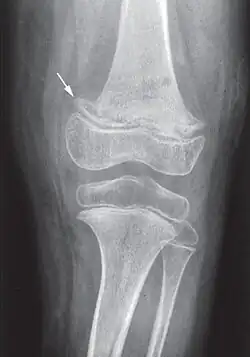

Elle débute par une perte d'appétit, un arrêt de la prise de poids, une pâleur, suivis d'un syndrome douloureux des membres entraînant agitation, cris et insomnie (pleurs à la mobilisation des membres). Les signes osseux sont au premier plan : à la palpation douce, on trouve des tuméfactions osseuses, surtout au niveau du fémur ou des articulations chondrosternales (entre le sternum et les côtes, parfois appelées le « rosaire scorbutique »). La gingivite n'apparaît qu'avec les premières poussées dentaires[23].

Les douleurs osseuses sont liées aux hémorragies sous-périostées. La radiographie peut montrer les troubles du périoste (hématomes sous-périostés) et de la structure osseuse (ostéoporose avec aspect en « verre pilé », la « ligne scorbutique » séparant la diaphyse des extrémités, élargissement de l'extrémité antérieure des côtes...)[23].